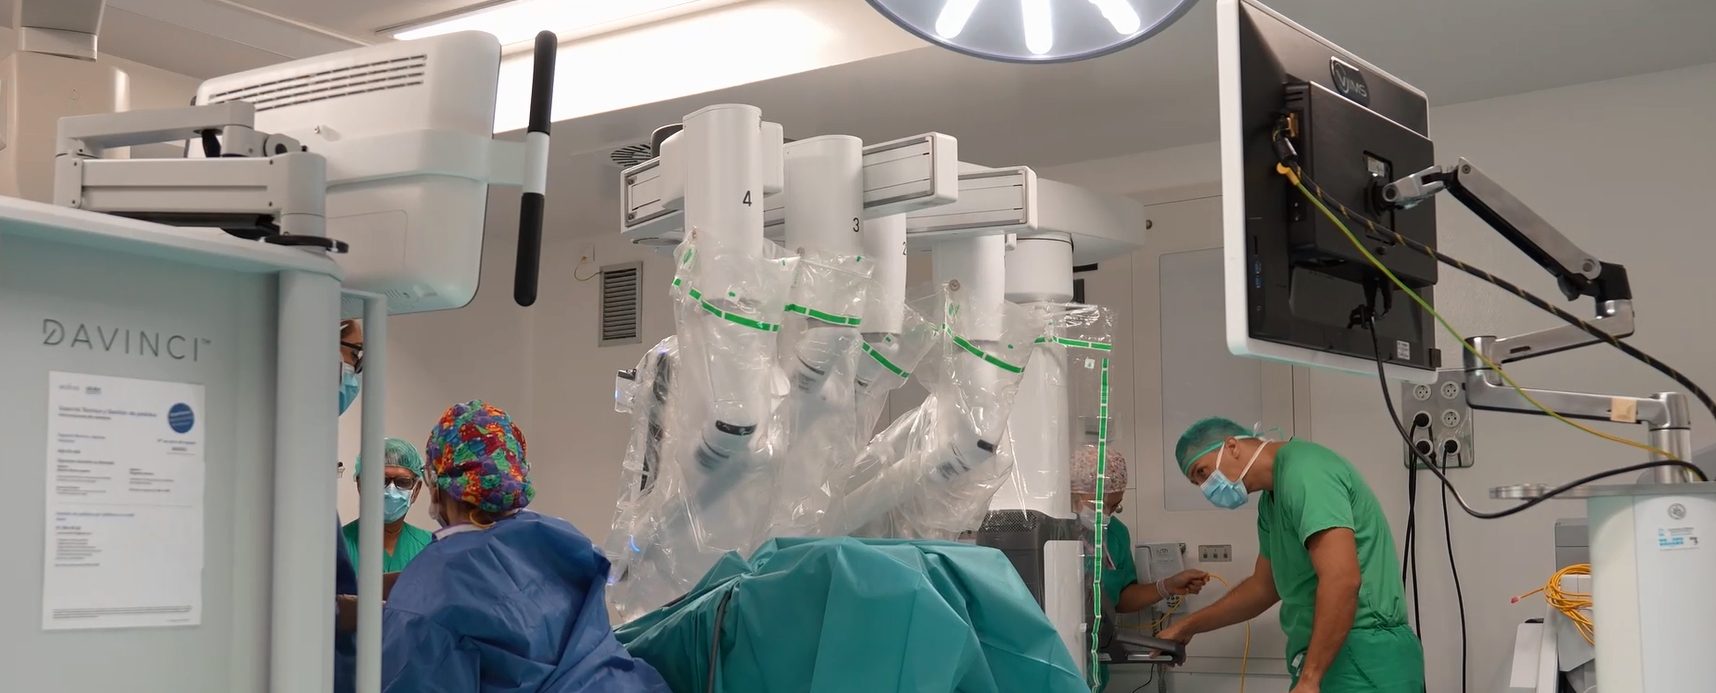

El Hospital Universitario Doctor José Molina Orosa de Lanzarote ha dado un paso decisivo hacia la medicina de vanguardia con la incorporación de la cirugía robótica, gracias a una inversión de 1,7 millones de euros. Se trata del robot quirúrgico Da Vinci Xi, que ya ha sido utilizado con éxito en las primeras intervenciones desde el 24 de septiembre.

La consejera de Sanidad, Esther Monzón, resaltó que la cirugía robótica permitirá a los pacientes acceder a tratamientos menos invasivos, con mayor precisión y una recuperación más rápida, mejorando la calidad asistencial y reforzando el compromiso con la innovación en la sanidad pública canaria.

El robot Da Vinci Xi está compuesto por tres unidades principales: la consola del cirujano, el carro quirúrgico y la torre de visión. Desde la consola, el cirujano controla los instrumentos con movimientos digitalizados que eliminan temblores, garantizando precisión y ergonomía. El carro sostiene los brazos quirúrgicos, mientras que la torre de visión centraliza el procesamiento y la visualización en 3D.

Según Juan De Diego, jefe del servicio de Cirugía, las primeras intervenciones se realizaron en cirugía general y del aparato digestivo con resultados exitosos. La incorporación progresiva permitirá ampliar el uso del robot a especialidades como urología y ginecología, manteniendo la excelencia quirúrgica del hospital y reduciendo los tiempos de recuperación para los pacientes.

Con este proyecto, el Hospital Molina Orosa no solo fortalece su capacidad tecnológica y quirúrgica, sino que consolida el esfuerzo de años del Servicio Canario de la Salud y del propio hospital por ofrecer la mejor atención sanitaria a los ciudadanos de Lanzarote.